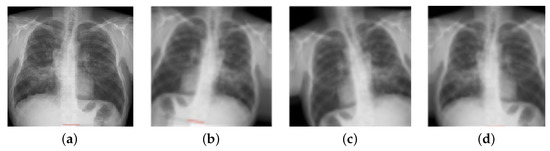

- Image Normalization: Different manufacturers of X-ray devices may provide different-looking X-ray images for the same patient. Overfitting to the device pixel distributions is quite a big problem in computer-aided diagnostic devices; therefore, it is standard practice to apply contrast normalization to minimize this problem. The general idea is to unify the distribution of pixels. This makes X-rays appear a little darker. This procedure generates a view that radiologists would not see in their standard workplace. Using the Reinhard and Macenko approaches, X-ray images were stain-normalized [43,48,49]. A reduction in the color discrepancies of X-ray images improves the classification accuracy of EfficientNet models.

- Data Augmentation: The normalized X-ray images were augmented before introduction into the EfficientNet model for training. The process of increasing the number of original images in a collection is known as data augmentation [38,50]. This strategy helps to eliminate the overfitting problem that arises when a model learns enough from the training data but cannot classify images of undetected X-rays. Table 3 illustrates the augmentation settings used on the stain-normalized X-ray images. In this study, the number of normal images was 1010, which is twice as many as the number of TB- and sarcoidosis-infected images. Therefore, the TB-infected images were augmented from 563 to 1126, and the sarcoidosis-infected images were increased from 231 to 462.